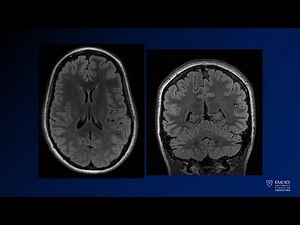

Diagnostic Cerebral Angiography